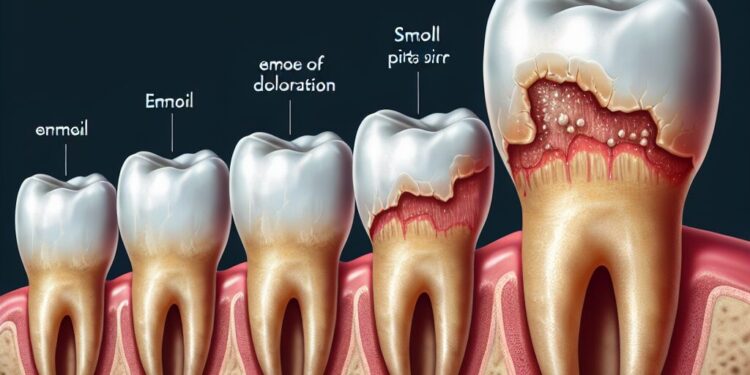

A erosão dentária é definida como a perda irreversível do tecido dental, causada pela ação direta de ácidos não bacterianos sobre a superfície do esmalte e, em casos mais severos, da dentina. Esses ácidos podem vir de fontes extrínsecas, como a alimentação, ou de fontes intrínsecas, como o refluxo gástrico.

Diferente do desgaste mecânico ou da abrasão dentária, que resulta do atrito ou escovação excessiva, a erosão é caracterizada pela dissolução química dos minerais do esmalte. Inicialmente, a substância mineral do esmalte é removida, deixando a superfície mais frágil e suscetível a outros tipos de desgaste.

Sintomas e sinais da erosão dentária

A erosão dentária pode se manifestar de maneiras diferentes dependendo da severidade e da localização das áreas afetadas. Entre os sintomas e sinais mais comuns estão:

- Alterações na aparência dos dentes: os dentes podem apresentar um aspecto translúcido, opaco, amarelado devido à exposição da dentina;

- Desgaste e achatamento da superfície oclusal: que pode acarretar alterações na forma dos dentes;

- Aumento da sensibilidade dental: especialmente ao frio, doce e ao toque;

- Cavidades superficiais: que podem evoluir para perdas maiores se não tratadas;

- Problemas estéticos: como manchas e alterações na cor.

O exame clínico permite avaliar visualmente o desgaste e a presença de alterações na superfície dentária. Manifestações típicas de erosão incluem o desgaste em áreas expostas a ácido, como faces palatinas dos dentes superiores em casos de refluxo.